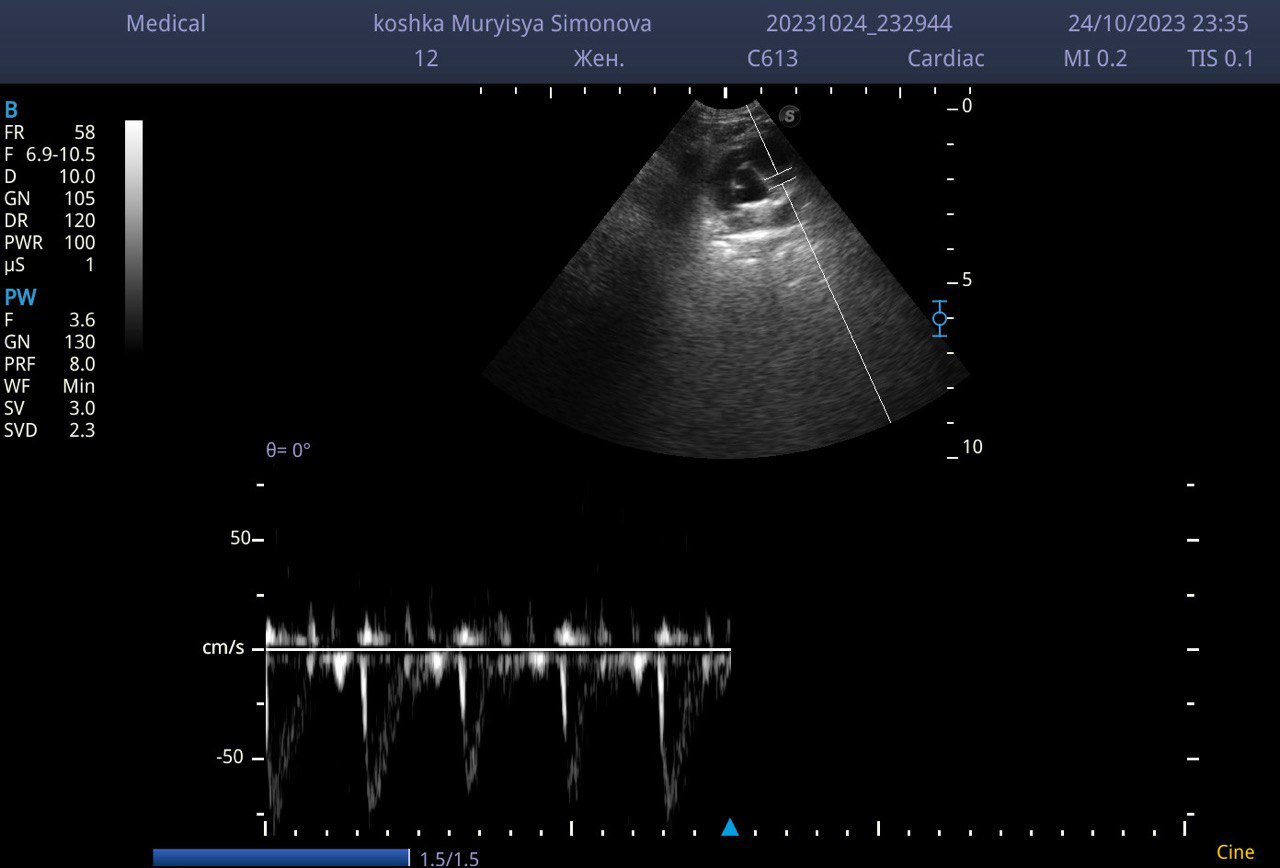

Кардиологический прием собак и кошек включает в себя:

- Эхокардиография

- ЭКГ

- Тонометрия (измерение давления)

Все три пункта, основа для получения информации о пациенте. Далее врач собирает анамнез жизни и предыдущего лечения и выдает развернутый протокол с рекомендациями и планом дальнейшего контроля.